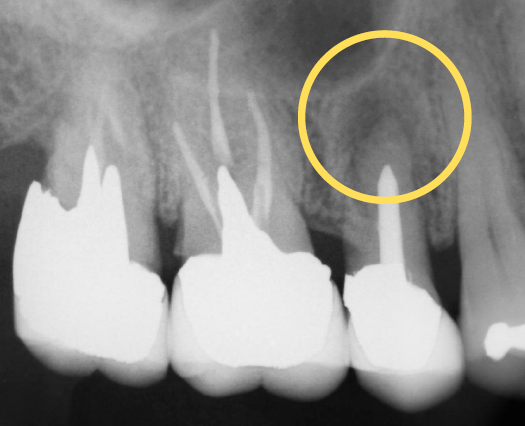

治療後の状態がこちらです。

マイクロエンドを行ったことで、根っこの病巣をしっかり除去できているのがレントゲンを見るとわかります。また、マイクロエンドを選択していただくと保険では扱うことのできない器具や薬剤を使用できるため、より再発のリスクを抑えることができます。今回の患者様は、ホワイトニングもご希望だったので、被せものの色を白く作成しています。そうすることで、他の歯との色味もなじみ患者様も満足されていました。